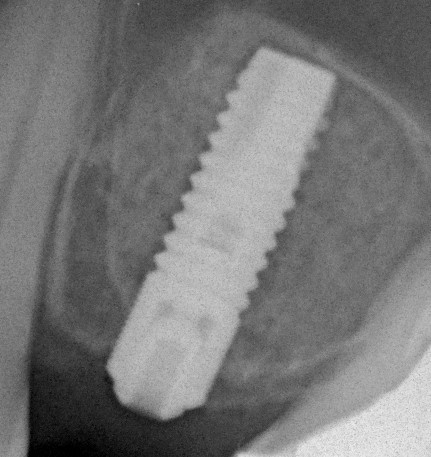

Синуслифтинг: что делать при перфорации слизистой оболочки гайморовой пазухи?